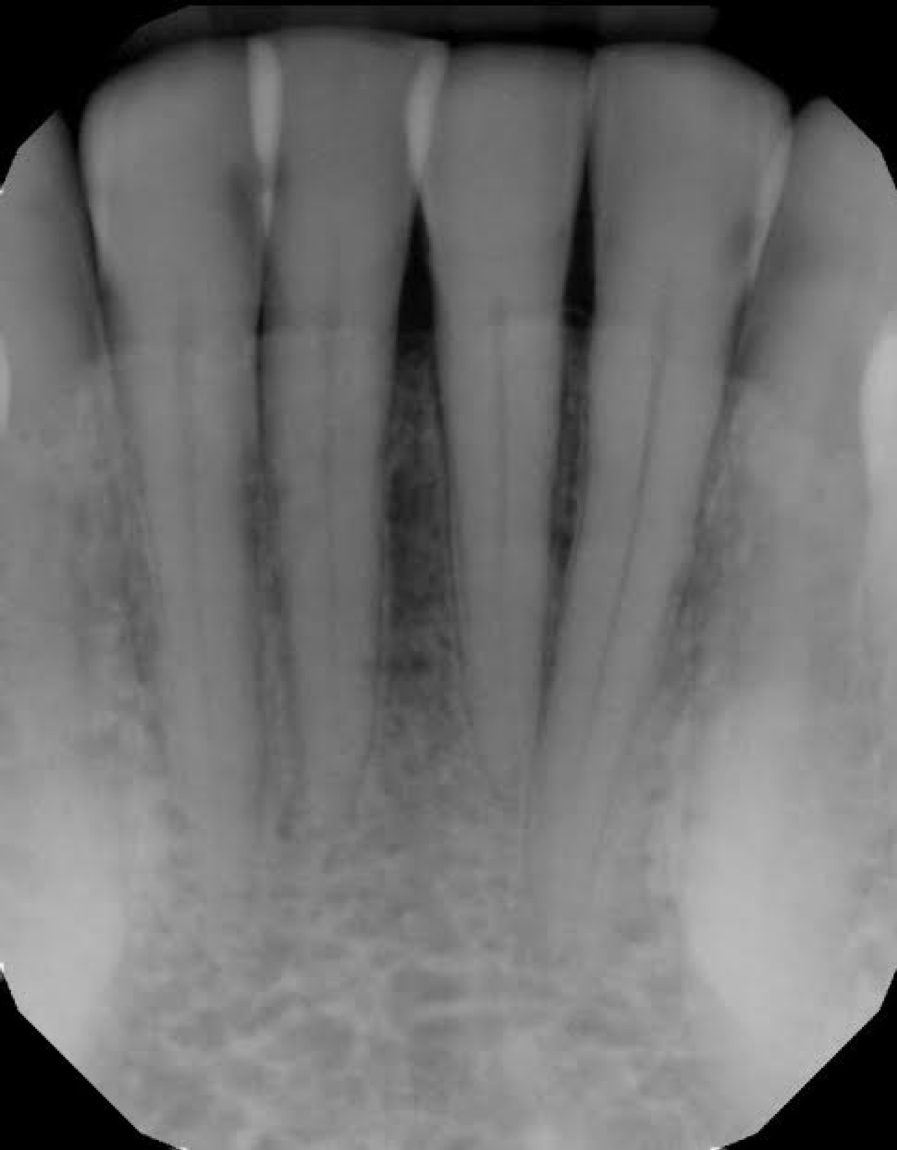

In another example, a young patient had been using e-cigarettes for five years. He started vaping as a method to quit smoking traditional tobacco products thinking vaping was a healthy alternative. Because of its ease of use, he smoked a cartridge of one of the more popular vaping products a day. Admittedly, he also drank energy drinks (high sugar content), stating that his mouth was often dry after vaping. This combination led to rampant decay with smooth-surface lesions and future tooth loss (figure 3).

Figure 3: Effects of e-cigarettes